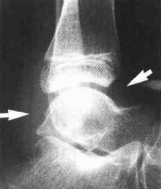

图2-1幼年型特发性关节炎(早期)

左踝关节诸骨质疏松,踝关节前后关节囊肿胀(白箭)

但无明显的关节软骨消失或软骨下骨质破坏表现